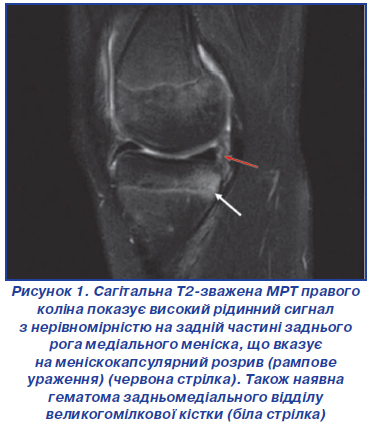

Інші, більш тонкі результати МРТ також асоційовані з рамповими ураженнями. Пацієнти з набряком на задньомедіальному плато великогомілкової кістки мають у 2,1 раза більшу ймовірність ураження рампи порівняно з пацієнтами з розривом тіла меніска [25]. У 72 % пацієнтів з ураженням рампи меніска присутній кістковий набряк у задньомедіальному відділі великогомілкової кістки (рис. 1). Вивчаючи МРТ, Kim et al. [27] описали ознаку «відкритого медіального меніска», яка є позитивною, якщо вертикальна лінія, проведена по дотичній до задньої сторони медіального великогомілкового плато, перетинає будь-яку частину меніска при колінному суглобі, зігнутому під кутом від 0 до 10º.

/50.jpg)